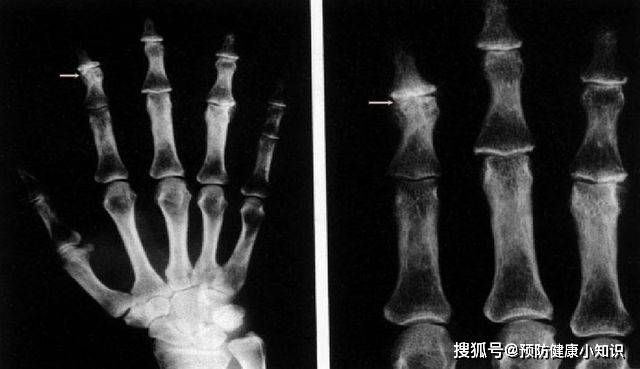

3、影像学检查

(1)X线平片骨关节

发现骨质疏松症、骨关节炎或骨软化等 , 多见于手术 。

【症状|肝豆状核变性是一种先天疾病,有家族史者,应进行基因检测】

文章图片